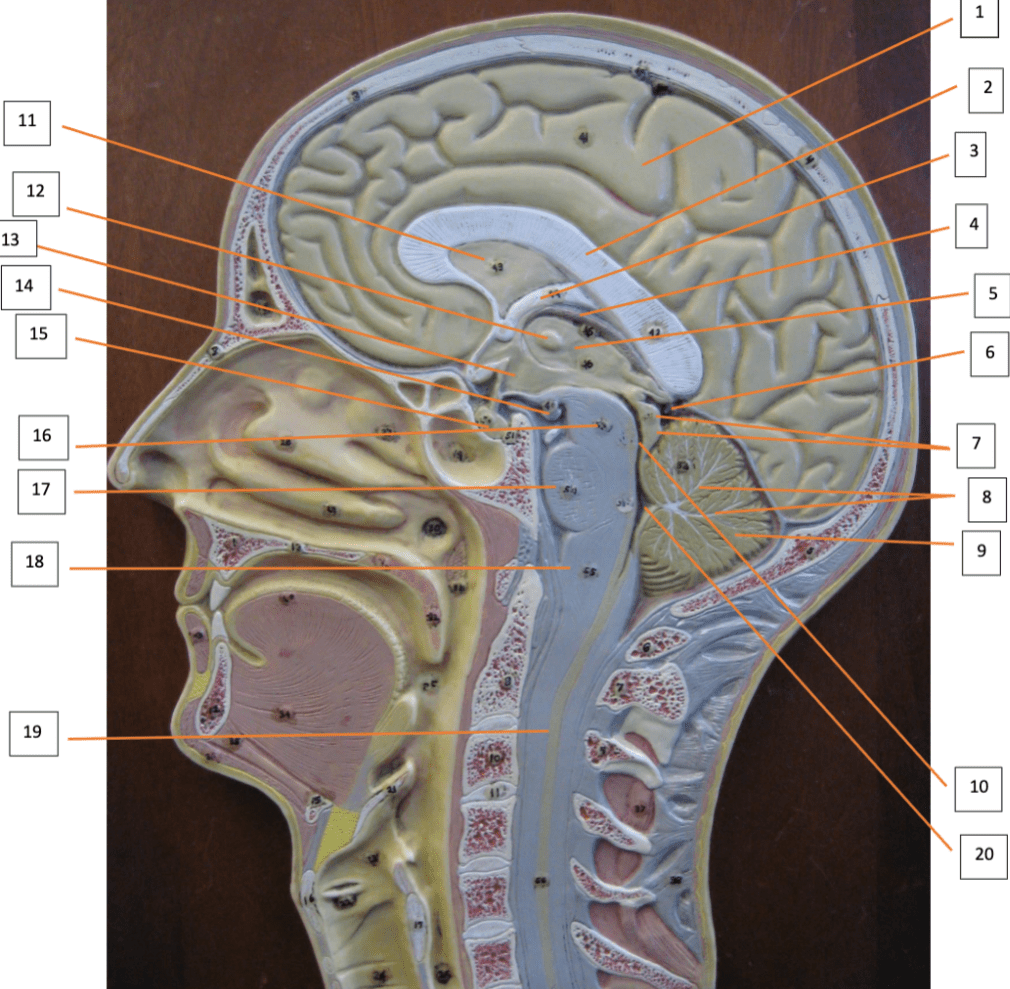

Label 2, 3, 7, 12

2: Corpus callosum

3: Fornix

7: Corpora quadrigemina

12: Intermediate mass of Thalamus

Label 3, 4, 6, 15, and 17

3: Choroid plexus – 3rd ventricle

4: Pineal gland

6: Cerebral peduncle

15: Mammillary body

17: Medulla Oblongata

Label 5, 8, and 13.

5: Optic chiasm

8: Trigeminal nerve

13: Abducens nerve